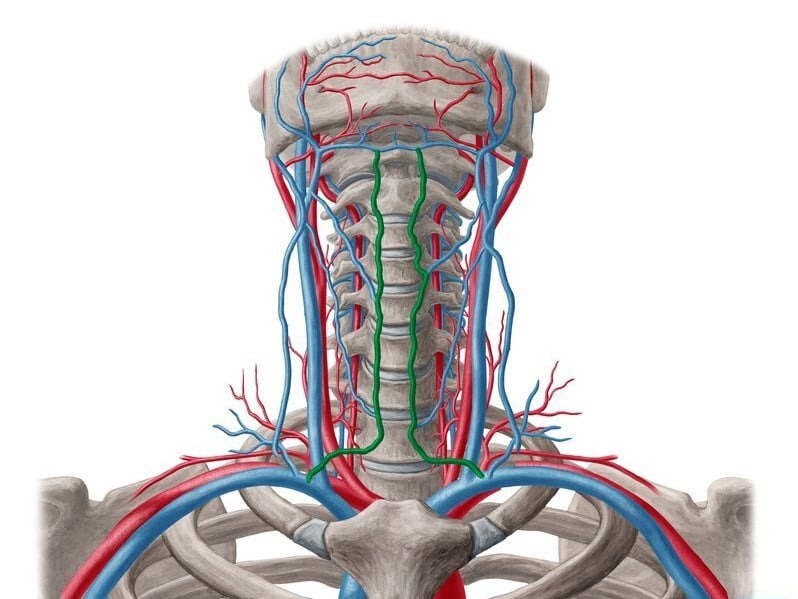

الوريد الوداجي بالإنجليزية “Jugular vein” هو وريد يحمل الدم كم منطقة الرأس و ينقله من خلال الوريد الأجوف العلوي الى القلب.

ارتفاع ضغط الشريان الرئوي: تحدث هذه الحالة عندما يرتفع الضغط في الأوعية الدموية بشكل خطير ، مما يتسبب في زيادة سماكة جدرانها وتيبسها ، مما يعني مرور كمية أقل من الدم. و هذا يمكن أن يضر بالجانب الأيمن من القلب ويزيد الضغط في الوريد الأجوف العلوي.

انسداد الوريد الأجوف العلوي: يمكن أن يحدث انسداد الوريد الأجوف العلوي إذا كان الورم ينمو في الصدر أو تتشكل جلطة في الوريد الأجوف العلوي يقيد تدفق الدم في الوريد.